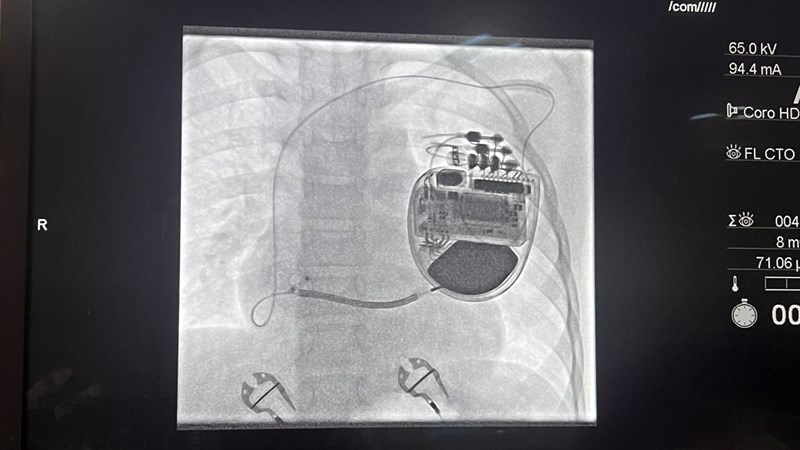

Arrhythmia Alliance Pace4Life will be traveling to Peshawar, Pakistan to provide life-saving pacemaker and device implants to individuals who could not otherwise access care and to train and upskill the local healthcare team.

Arrhythmia Alliance Pace4Life (A-A P4L) is a charity that donates cardiac implantable devices and other medical resources to people in need in Low- and Middle-Income Countries (LMIC) who otherwise would not be able to afford the lifesaving treatments. We source devices, identify viable clinics in LMIC countries, set up programmes at these clinics and train personnel, organise pacing missions, and provide ongoing online support to those programmes.